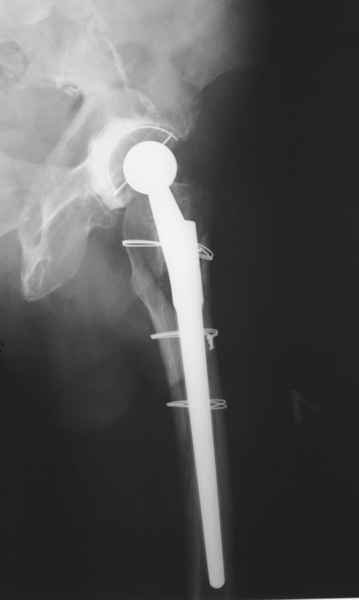

Уважаемые коллеги, продолжая дискуссию, начатую на "Вреденовских чтениях", хочу сказать, что принципиально сущестует два возможных варианта лечения.

1.Остеосинтез на ножке. Мне кажется, что применительно к этому случаю малоперспективный вариант. Синтез хорош, когда можно его выполнить в малоинвазивном исполнении и достигнуть стабильности. Действительно, если ножка б/цементной фиксации после этого не будет иметь фиксации, то ревизия не будет иметь проблем. В представленном случае стабильность синтеза сомнительная, а проведение доп.иммобилизации приведет к контрактуре суставов.

2. Применение ножки дистальной фиксации, мы отдаем предпочтение ножке Вагнера с фиксацией проксимального отдела на ножке. Более травматичное вмешательство, но при стабильной фиксации ножки реабилитация идет в обычном режиме.

Хочется показать два подобных случая, П-ка З. 72 лет и п-т Г. 80 лет. Сразу принимаю замечание, что это были ножки цементной фиксации, просто под руками не было бесцементника.

Пациента удалось осмотреть недавно. Достигнутый результат сохраняется. Перелом бедра сросся. Конечность опорная и безболезненная, ходит без трости. Ножка, похоже, реинтегрировалась, как и надеялись. Снимки и фото в приложении. Комментарии приветствуются.

Надо ли что-то делать дальше, как полагаете? Убрать винты? Убрать "удлинитель ножки"? Или оставить все, как есть? Спасибо заранее.